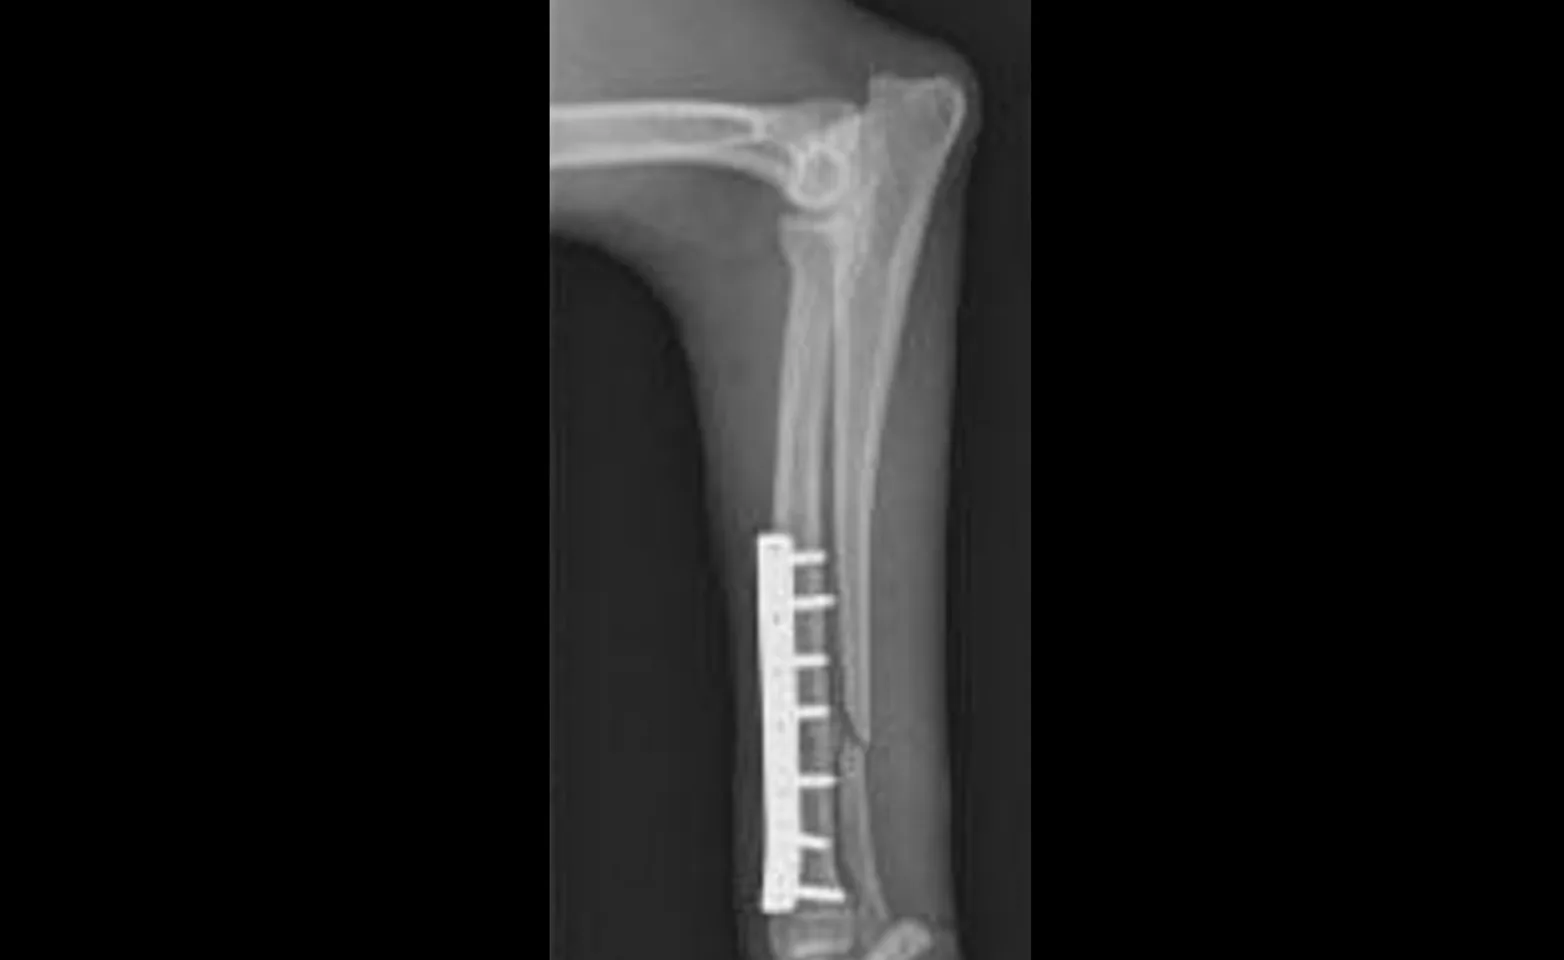

Placement of a cast or splint alone or combined with an IM pin does not provide for rotational stability and has a high incidence of brous nonunion formation. Ideally, the fracture segments should be anatomically reduced and stabilized with a plate and screws.

At the DVSC, we often use mini plates and screws to repair these fractures. The small plates minimize the chance for stress protection of the bone and reduce the need for implant removal. However, because of the small size of the plates, we provide splint support for the first four weeks postoperatively to minimize the chance for implant failure. With surgical application of the plate and screws, the incidence of abnormal bone healing is low.